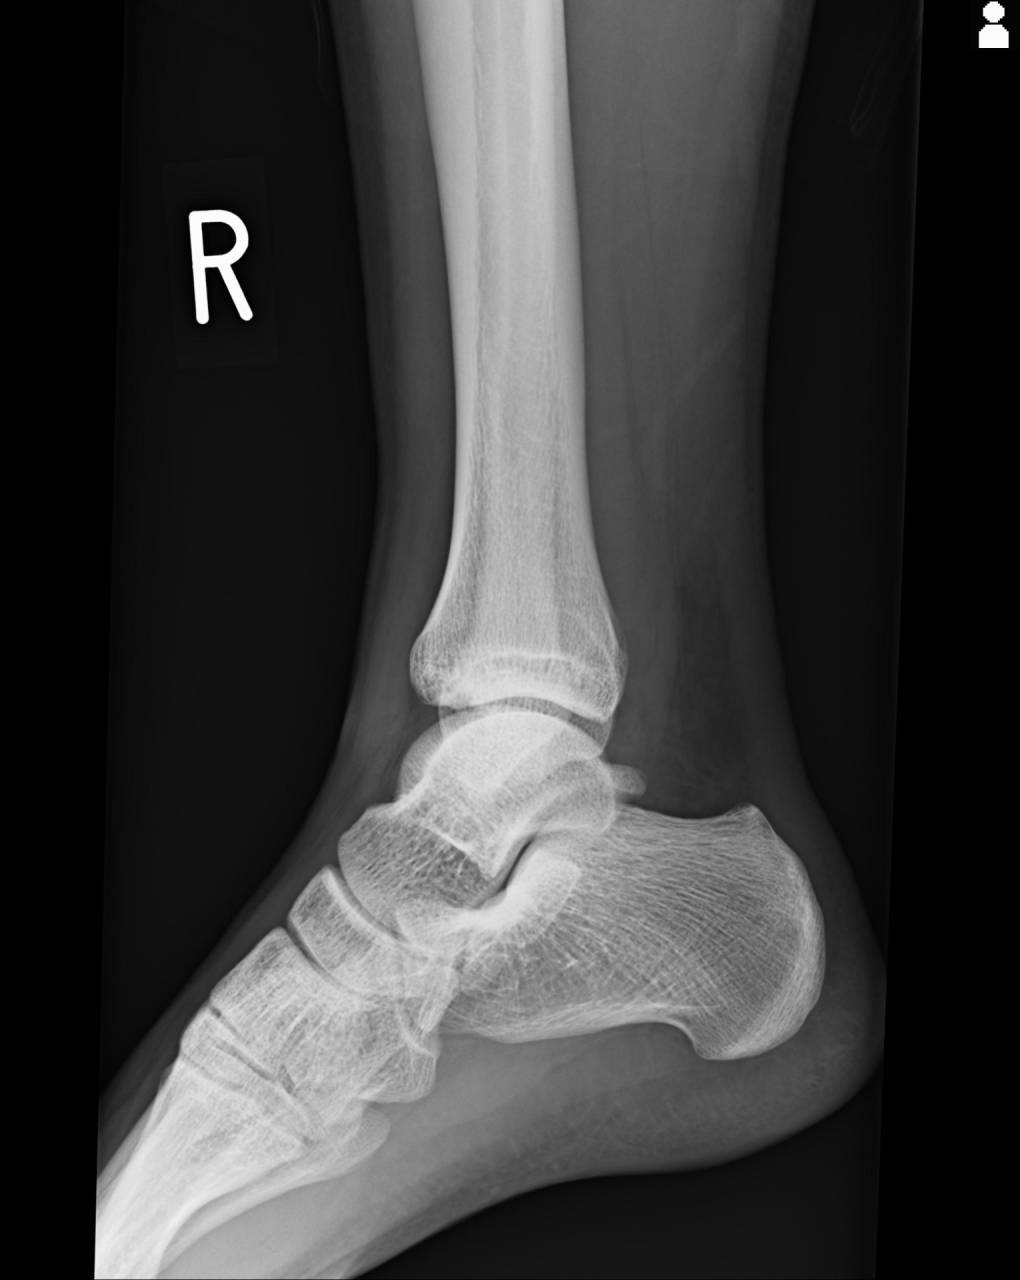

骨折が疑われるので当整骨院が提携している病院にてレントゲン検査を依頼しました。

撮影した画像を確認すると脛骨AITFL腓骨付着部のチロー骨折と外果にも骨損傷があり骨折として施術をしていきます。

チロー骨折は不完全に治すと関節障害につながる可能性が高いので、注意が必要になってきます。

距骨の亜脱臼は整復されているのも確認でき、足関節の可動性も上がり健側の左と比較しても左右差が減り20度まで背屈可能になりました。